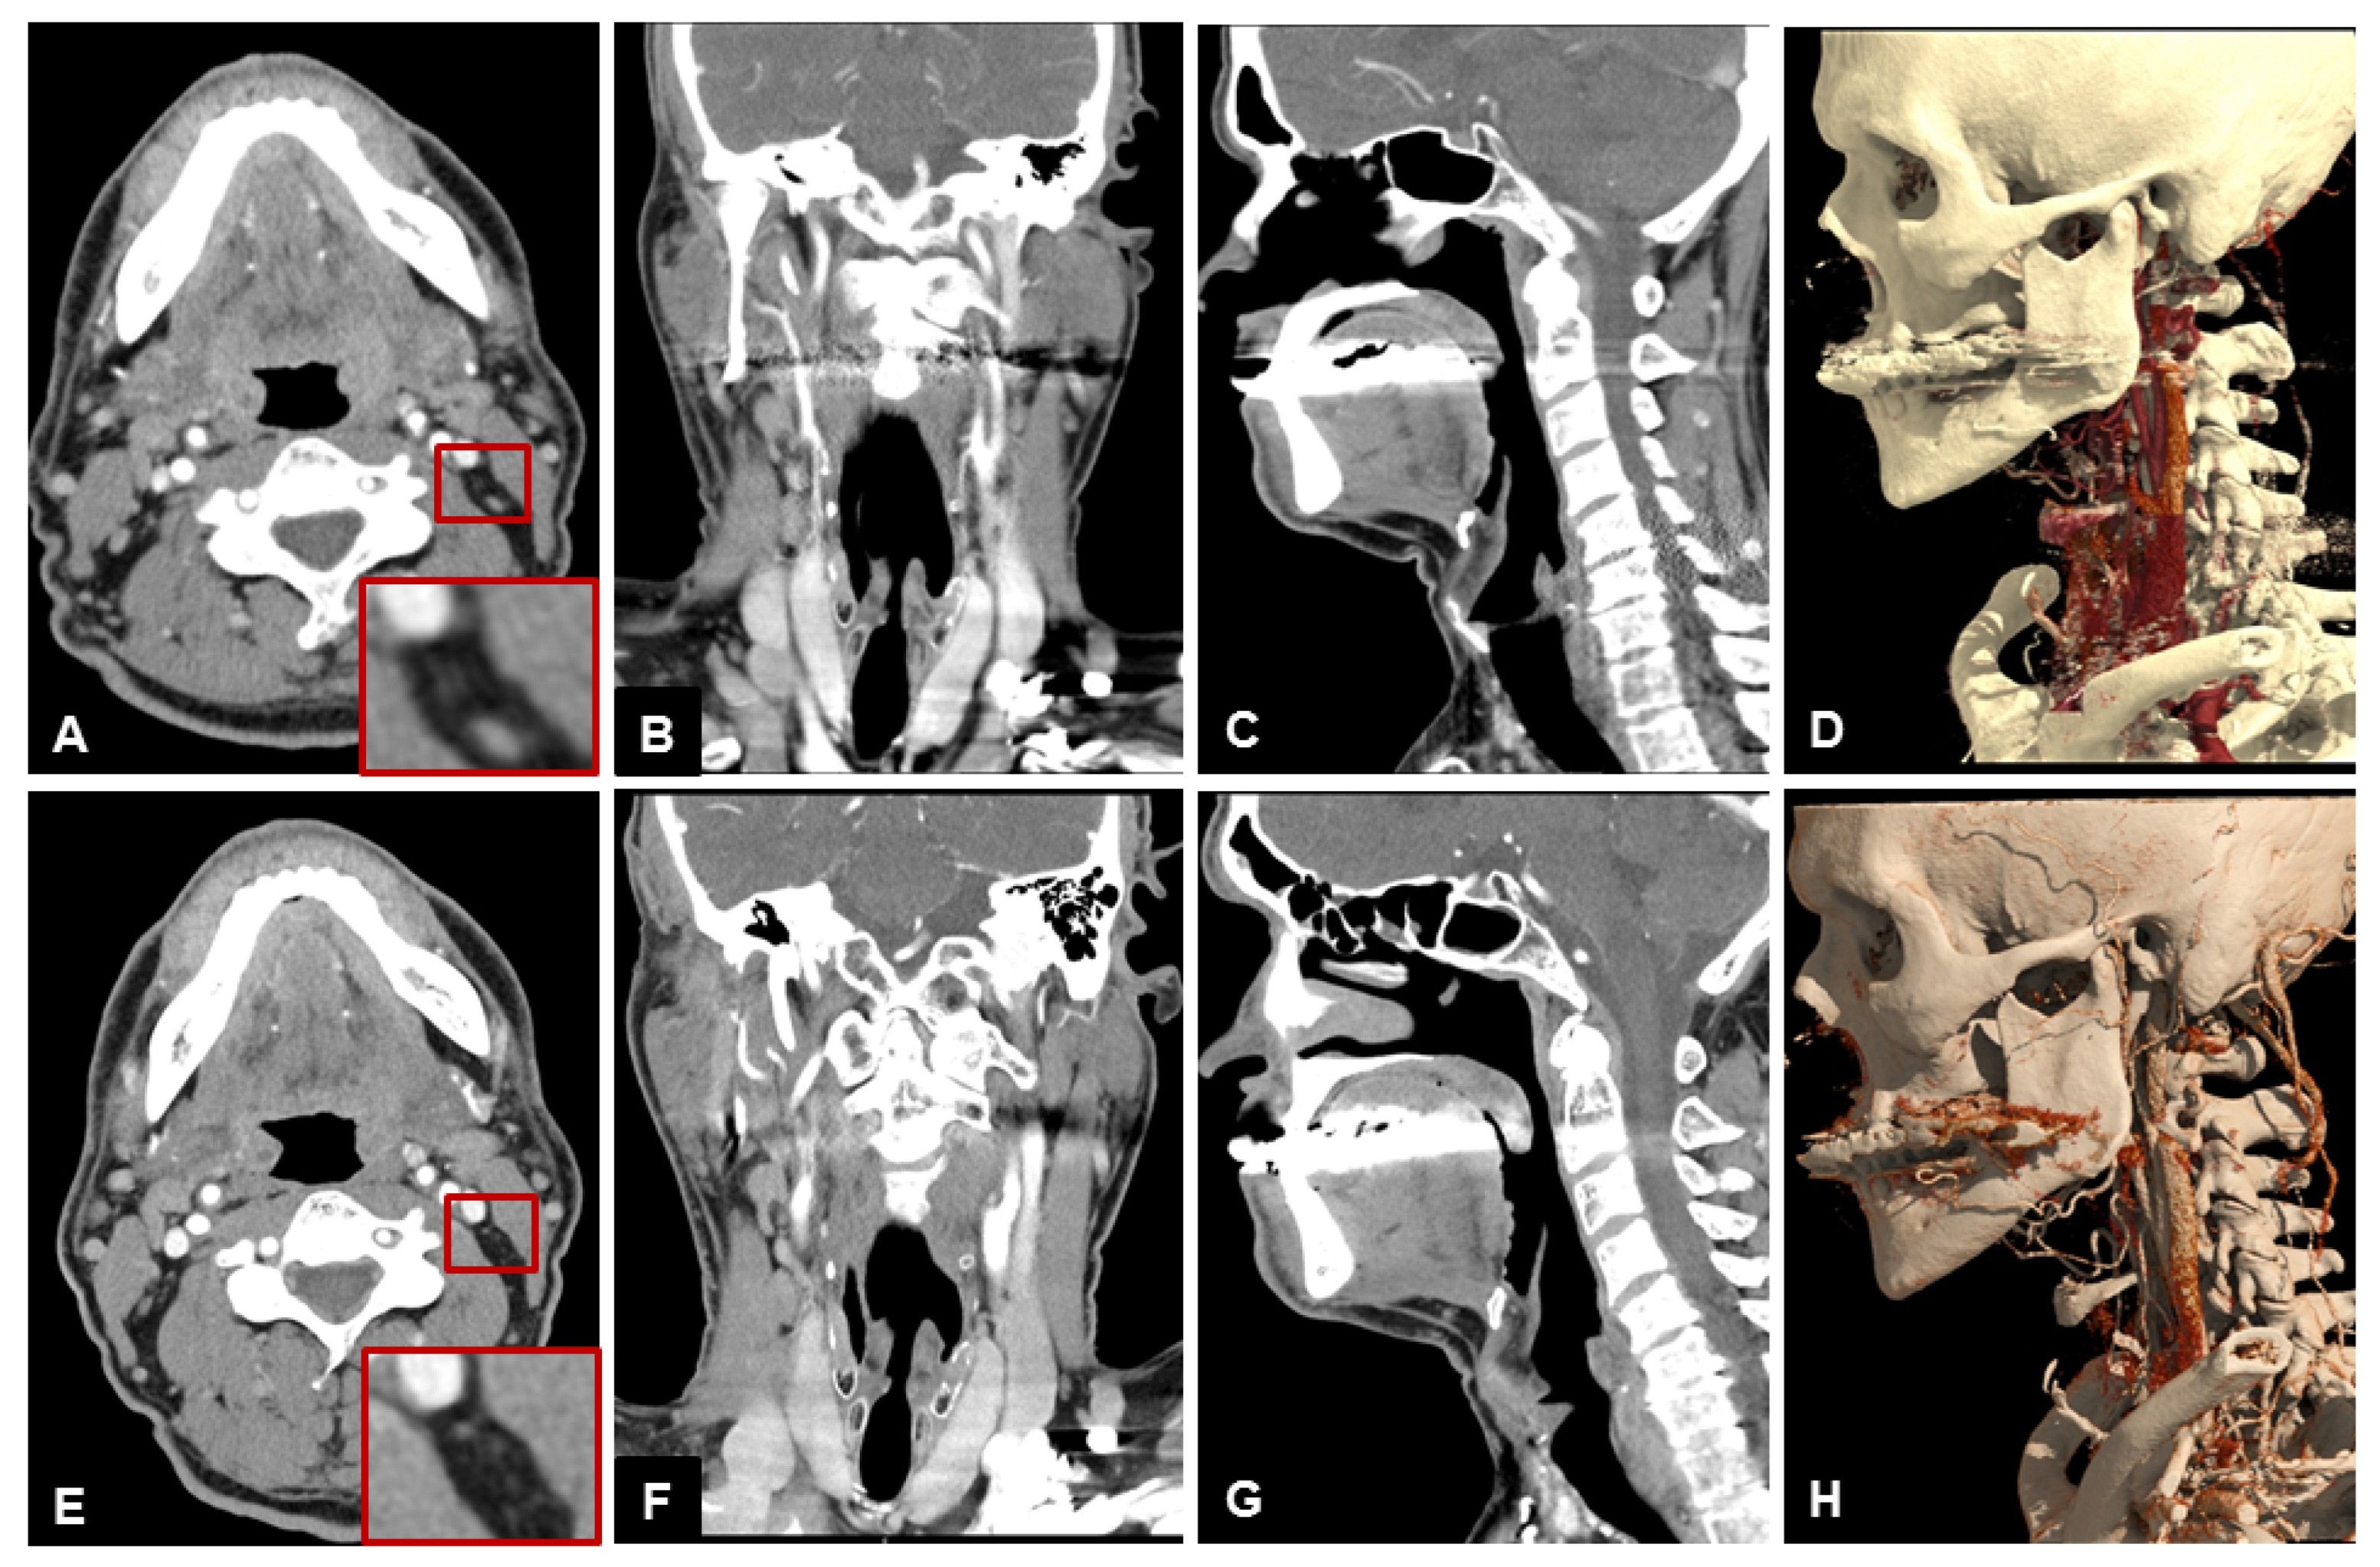

Table 3 lists the scores of both readers for subjective image quality in detail. Patient examples are given in Figure 4, Figure 5 and Figure 6.

Figure 4. Example of a 79-year old male patient with a squamous cell carcinoma of the right lower jaw. Patient initially refused surgery, thus a 3-months follow-up examination was performed. Note the clear depiction and hypervascularization of the tumor margins and the lower noise of UHR-CT, especially in the axial plane. In the coronal reconstruction you can beautifully depict the tumor infiltration of the perimandibular fat and the contours of the sublingual space. (A) axial 3 mm reconstruction NR-CT, (B) sagittal 3 mm reconstruction NR-CT, (C) coronal 3 mm reconstruction NR-CT, (D) best possible 3D-reconstruction NR-CT, (E) axial 3 mm reconstruction UHR-CT, (F) sagittal 3 mm reconstruction UHR-CT, (G) coronal 3 mm reconstruction UHR-CT, and (H) best possible 3D-reconstruction UHR-CT.